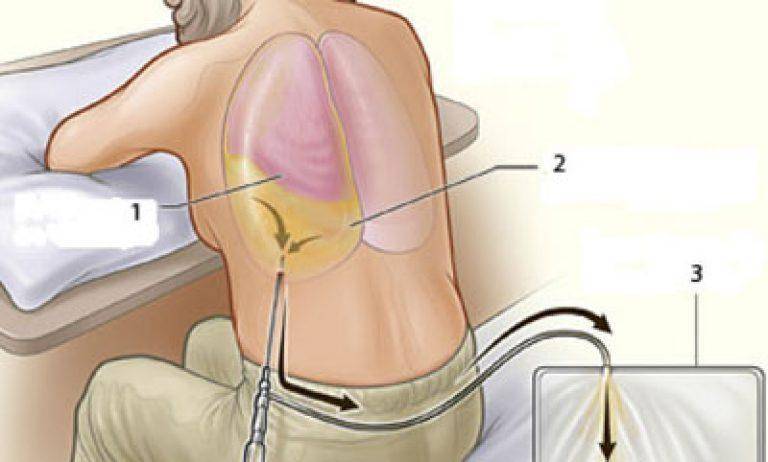

Симптомы и причины скопления воды в легких